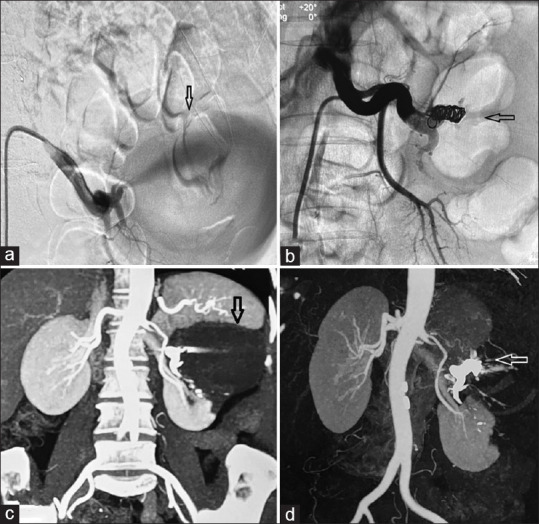

A 52-year-old female presented with a history of left partial nephrectomy performed 1 year ago for a left renal mass. She was asymptomatic and was under post-operative follow-up. A contrast-enhanced computed tomography scan of the abdomen was obtained which revealed a large renal artery pseudoaneurysm (of size 79 mm ×67 mm ×78 mm). In view of large size, therapeutic angioembolization was performed safely without any post intervention complications.